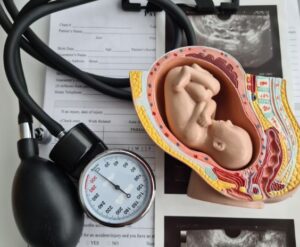

The chemical abortion pill is now more accessible than ever, available online, in pharmacies, and even by mail. It’s marketed as quick, easy, and private. But behind that convenience is a baby fighting for life and a woman in crisis, scared and searching for hope. Women are now being reached earlier, often before they’ve had a chance to see an ultrasound or talk to someone who will truly listen. Many are overwhelmed and convinced that abortion is their only option.